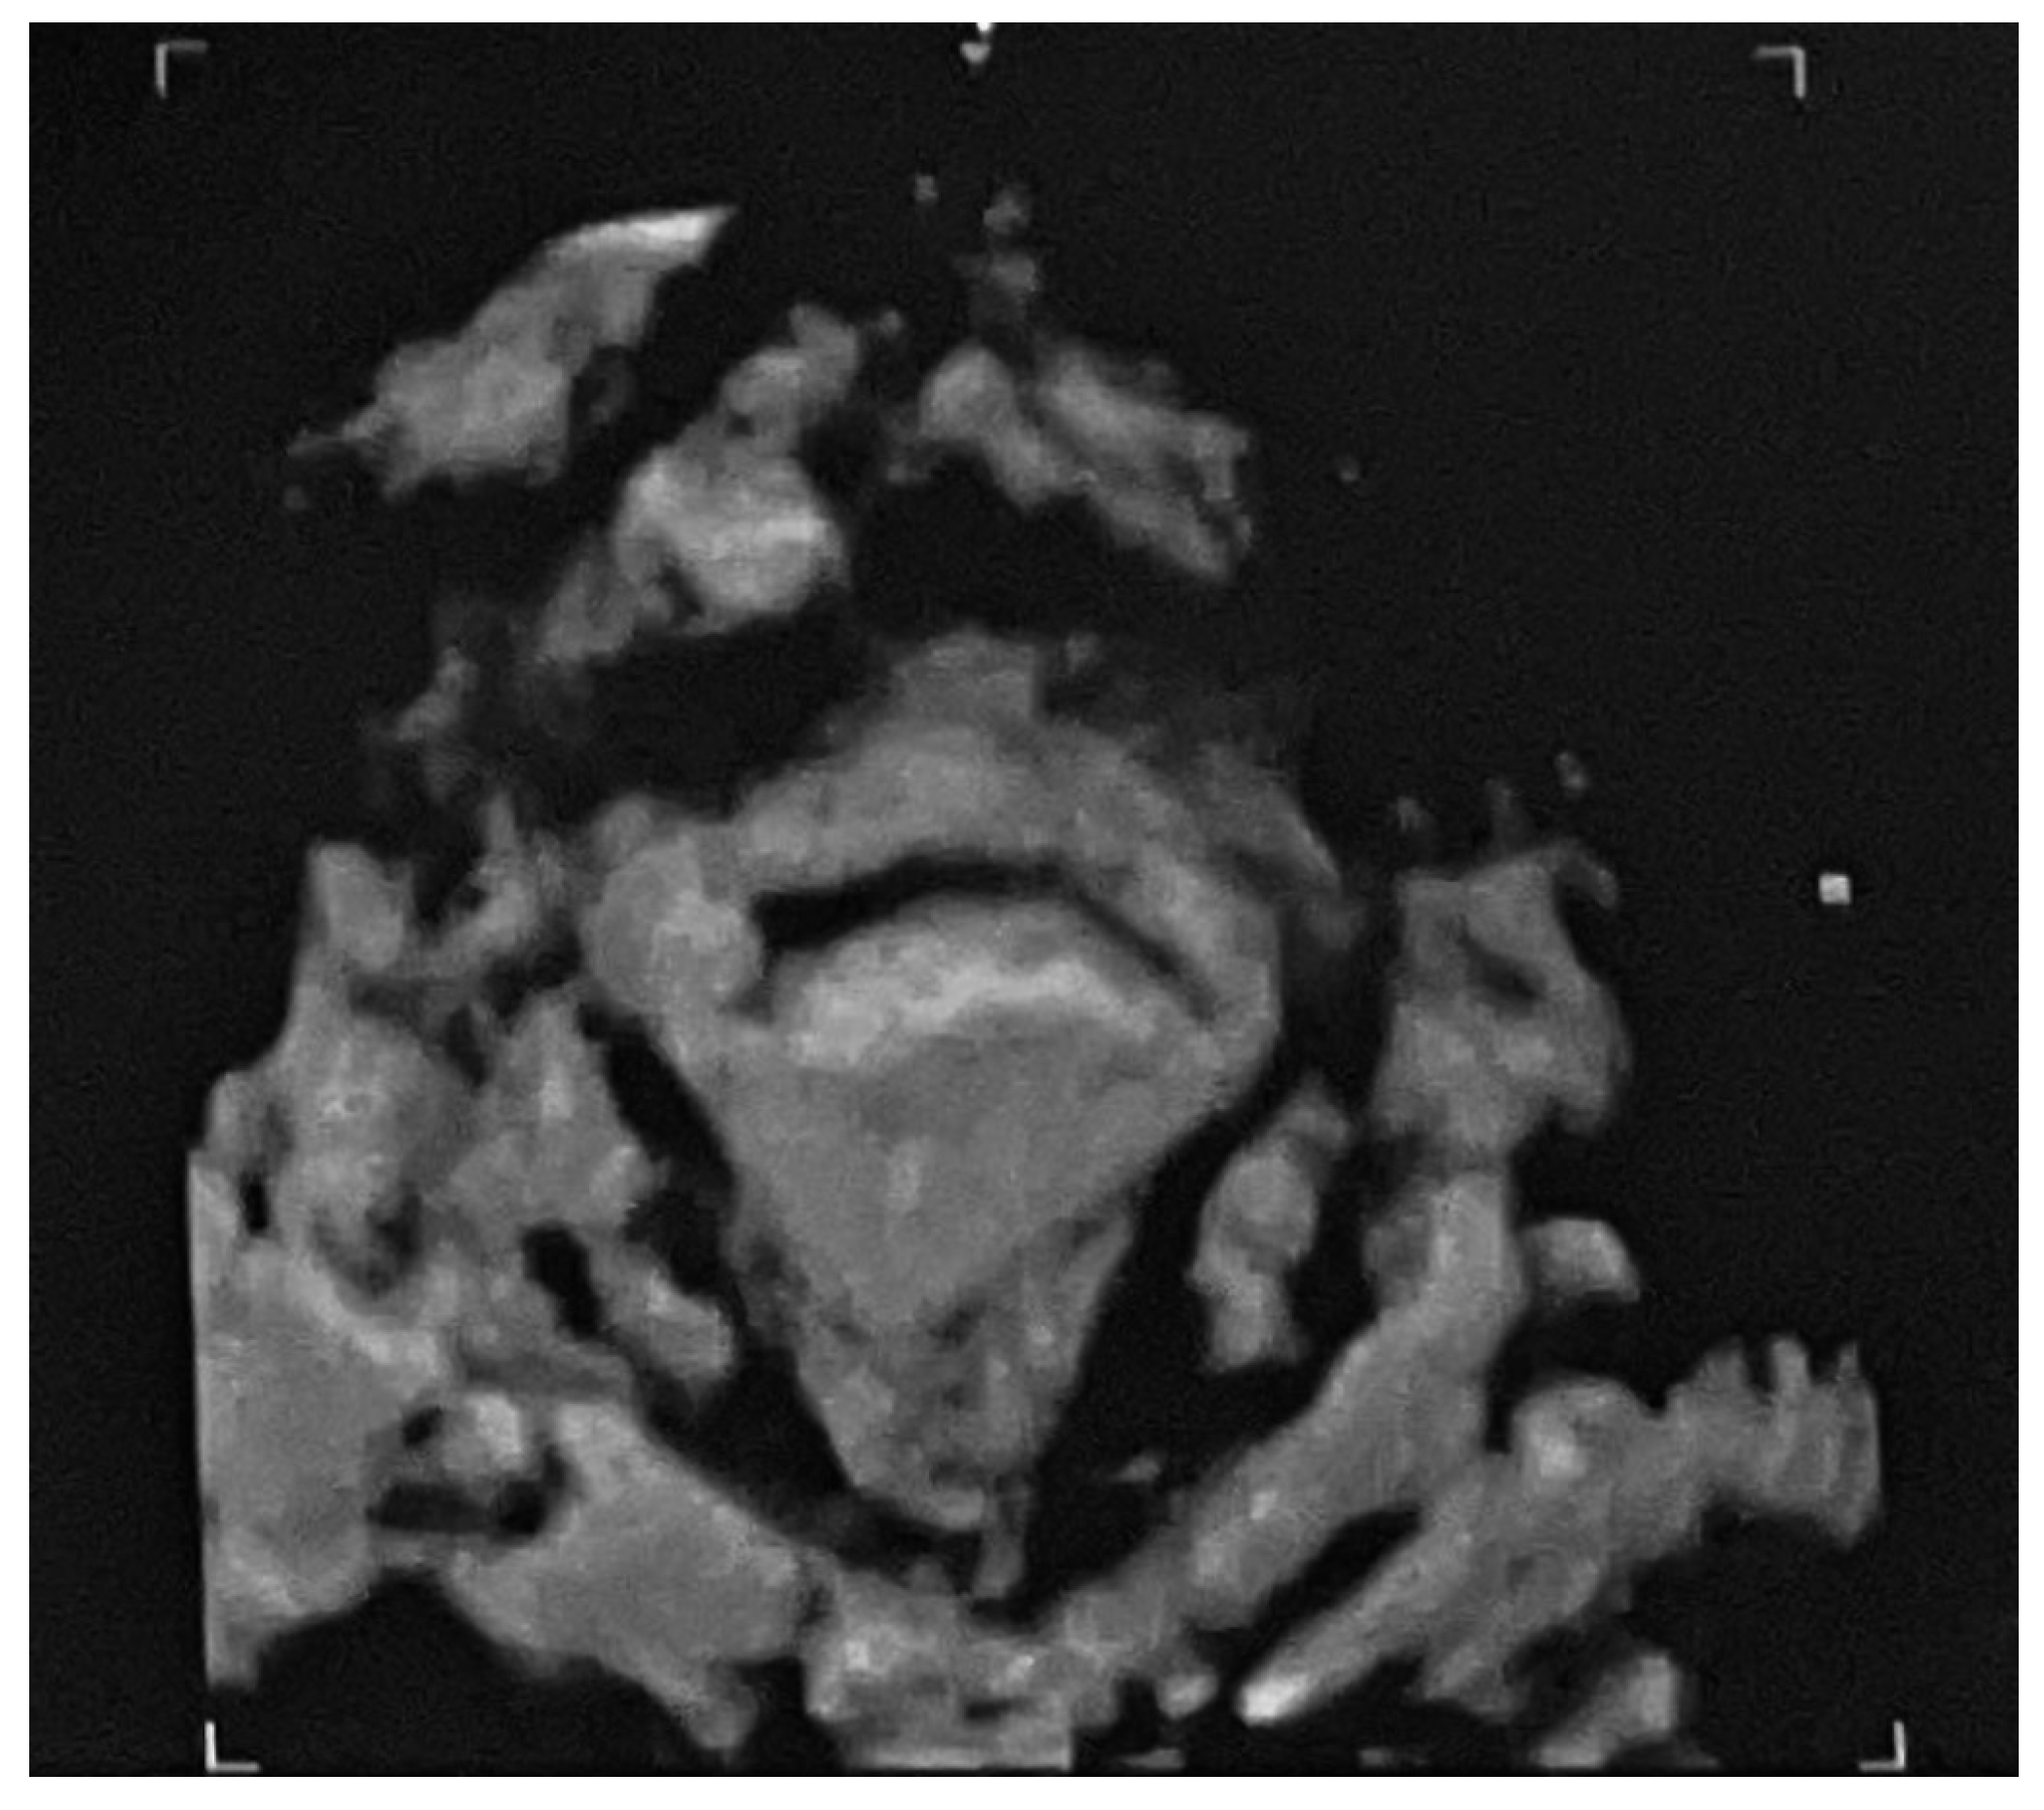

2. Case Presentation